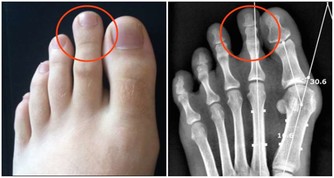

一、腳溝炎是什麼?

腳溝炎,是指腳指甲在受到外界的擦傷、刺傷、割傷後。因為沒有得到及時的處理,而受到局部的感染,細菌堆積,導致甲下發生膿腫,這是腳溝炎最主要的病因。此外,趾甲剪得太短或長期不剪趾甲、長期穿不合適的鞋子也會造成腳溝炎的發生。

(1)若趾甲有輕微損傷時,可以用碘酒進行消毒,用創可貼進行包紮,防止進一步感染。

(2)可外敷三黃散或者魚石脂軟膏,必要時可服用抗生素藥物。

(3)如果已經出現甲下化膿,應當到醫院去及時切開或將趾甲拔去,擠出膿液。